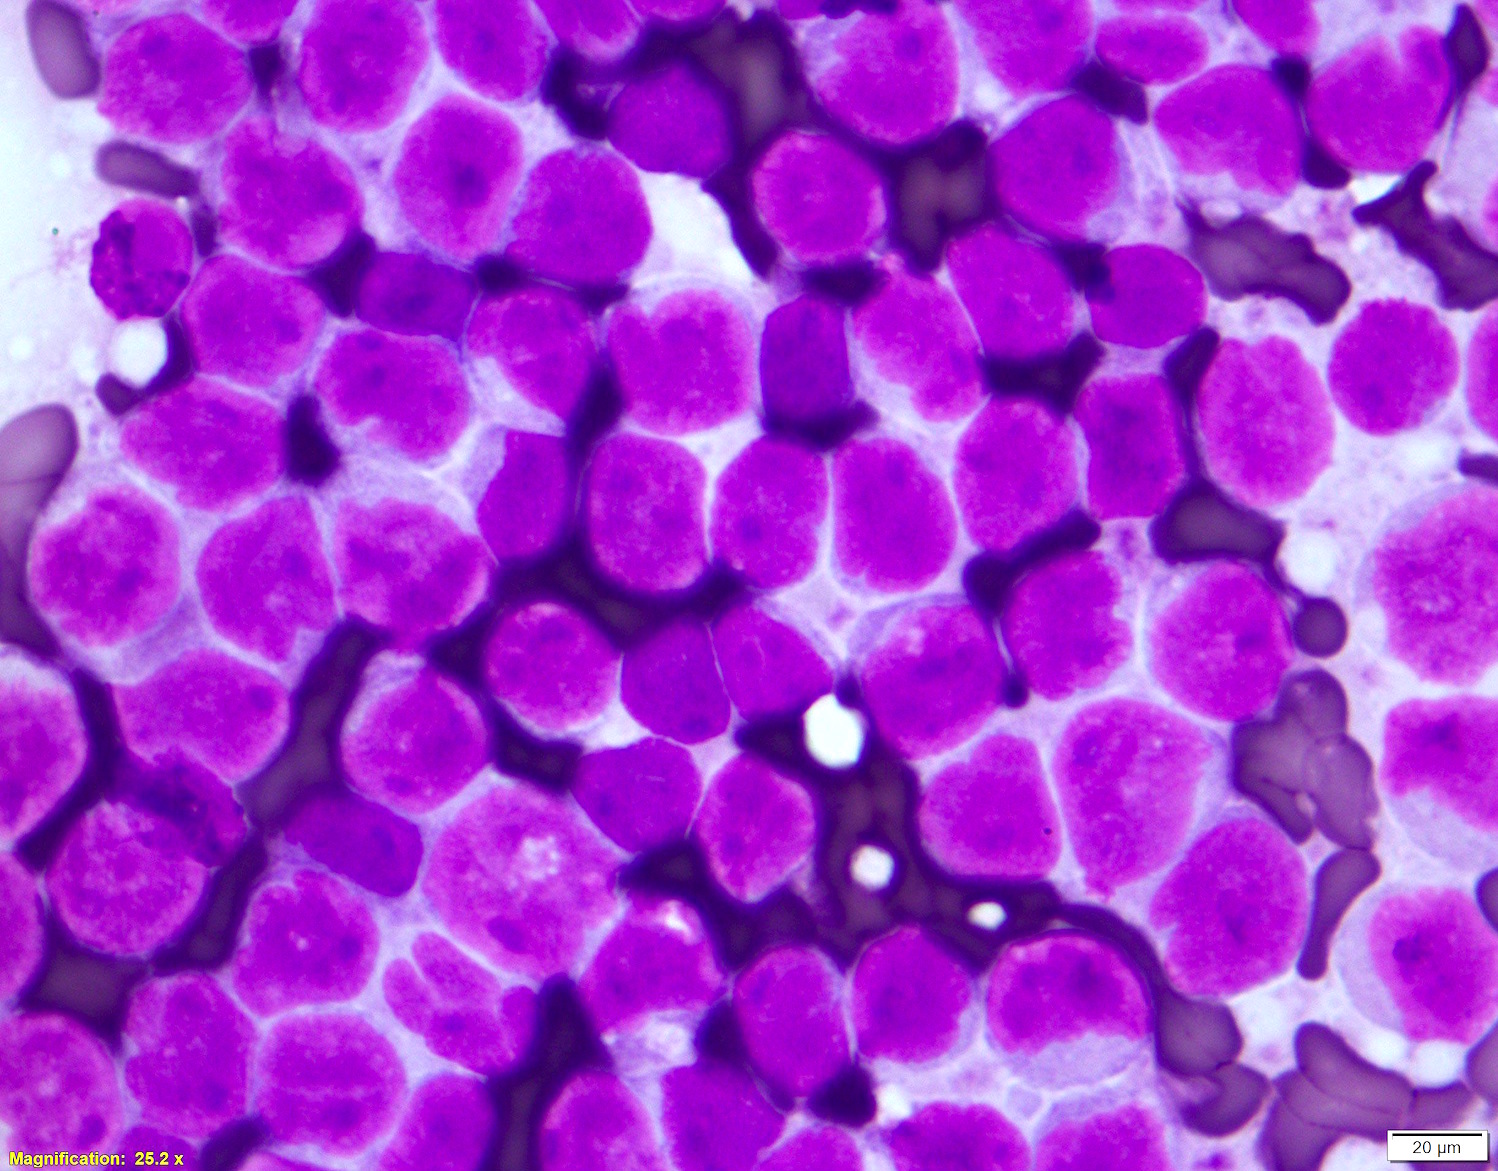

Microscopic (histologic) description

- Blastoid variant

- The growth pattern is usually diffuse

- Less frequently nodular pattern

- Starry sky appearance common in low power

- Intermediate sized cells

- Monotonous population

- Immature chromatin

- Scant cytoplasm

- High mitotic rate > 20 - 30/10 high power fields

- Resembles, in part, lymphoblastic lymphoma

- Pleomorphic variant

- Variable size / heterogenous cell population including large cells

- Prominent nucleoli +/-

- High mitotic rate often seen

- At least 10 mitoses per 10 high power fields and often higher rates

- Resembles, in part, diffuse large B cell lymphoma